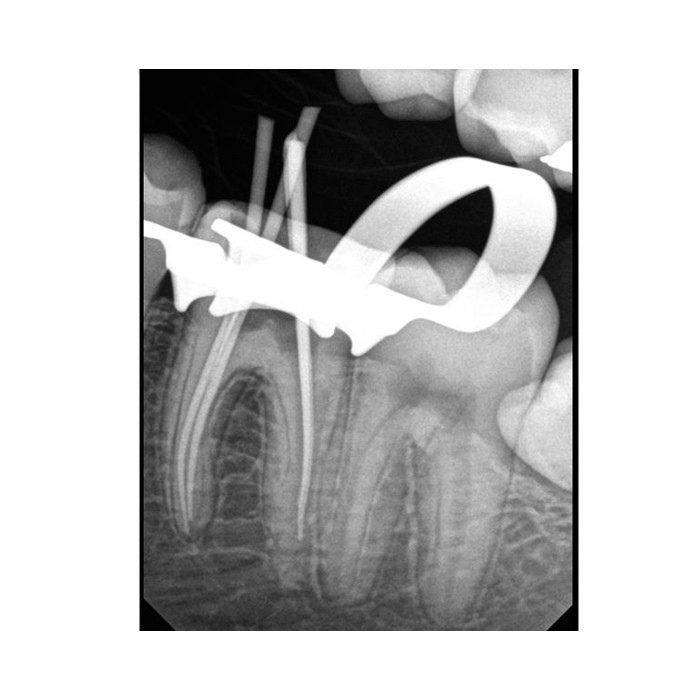

Радиовизиограф Carestream Dental RVG 6200: Цифровая четкость для уверенной диагностики

Радиовизиограф Carestream Dental RVG 6200 — это современное цифровое решение для внутриротовой рентгенографии, созданное для повышения эффективности и точности работы стоматолога. Он приходит на смену устаревшей пленочной технологии, предлагая мгновенный результат, превосходное качество изображения и значительное снижение лучевой нагрузки на пациента.

Ключевым преимуществом RVG 6200 является его высокое разрешение — 24 пар линий на миллиметр. Это означает исключительную детализацию снимков, позволяющую визуализировать мельчайшие анатомические структуры, начальные кариозные поражения, особенности корневых каналов и состояние костной ткани.

Система проста в интеграции в практику. Она состоит из внутриротового датчика (сенсора), который подключается к компьютеру через интерфейсный модуль. Получение изображения занимает считанные секунды после экспозиции, что ускоряет процесс диагностики и принятия клинических решений.

- Высокое диагностическое качество: Разрешение 24 lp/mm обеспечивает четкость и детализацию, необходимые для точной диагностики. Цифровое изображение можно обрабатывать: изменять контрастность, яркость, увеличивать интересующие области.

| Типичная область применения | Прицельная внутриротовая рентгенография: диагностика кариеса, контроль эндодонтического лечения, оценка состояния пародонта, анализ ретинированных зубов. |